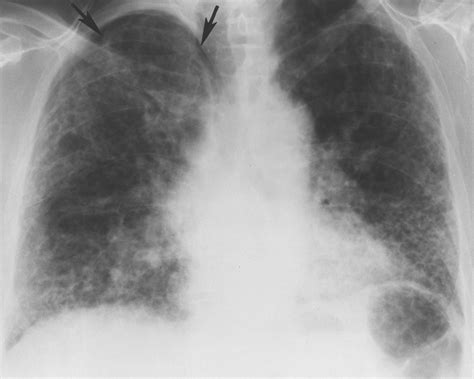

• Chest X-ray or CT scan

• bird fancier lung x ray

• bird fancier's lung radiology